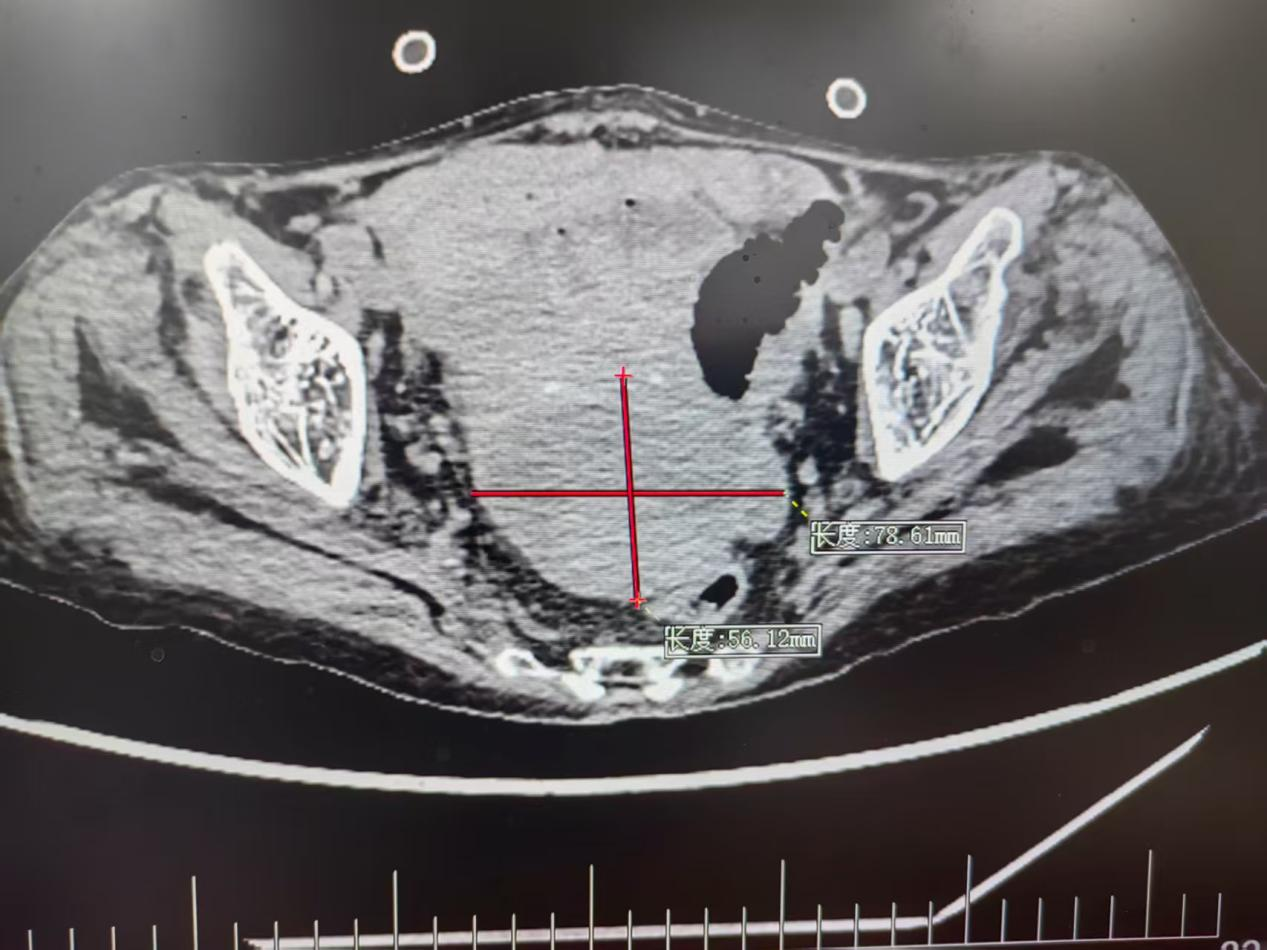

CT显示脓肿位置(红色“十字”部分)

张奶奶的求医路充满波折。不久前,她因“结肠癌破裂出血”紧急入院,胃肠外科团队紧急手术才将其从死亡线上拉回。可术后第23天,新的危机突袭:检查发现,张奶奶下腹部的子宫直肠凹(道格拉斯腔)里,长了一个大小约7.0×6.5×6.0cm的脓肿,这个深藏在盆腔深处的“感染炸弹”,若不及时处理,极可能引发全身性感染,再次威胁老人生命。